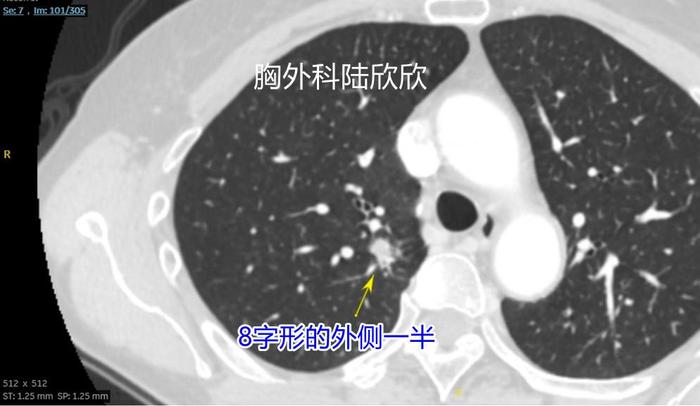

上面两张图,再往下至薄层CT的101层面,可见右上肺混合磨玻璃结节的外侧半,是这个8字形磨玻璃结节的外侧半。在这个平面以实性成分为主磨玻璃成分基本上在实性成分周边。在这个层面测量结节大小为14毫米,这个大小也是错误的。实性成分中心的平均CT值为+43,仍然很高。